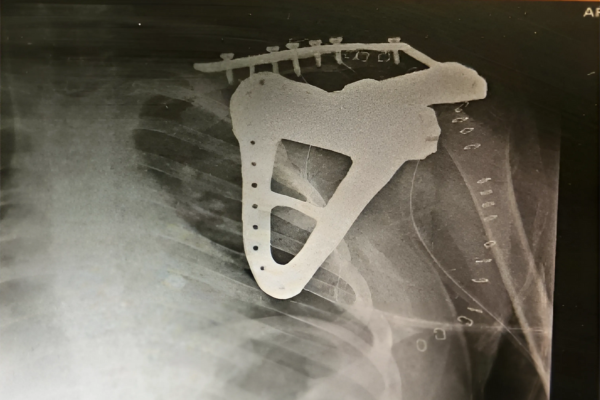

Dr. Ravi, India’s leading Orthopedic surgeon in Gurugram, Haryana decided to resect the tumor along with placement of 3D printed Implant. An encapsulated mass was found measuring 7 X 5 X 5 cm involving left Scapula and surrounding tissues, extending from base of acromion process to the scapular process. Incredible team discussed with Dr. Ravi, the designing and entire manufacturing process. It was initially started with surgical planning and case stimulation with the help of US FDA & CE approved Materialise Mimics software by superimposing CT & MRI DICOM data. Once the planning was finalized, the customized implant was designed along with UHMWPE poly liner matching the humerus head. Read more

Implant was manufactured under ISO 13485 guidelines & tested to give an accurate fit & utmost safety. Once the resection was done, customized implant from 3D Incredible was implanted.

The Polypropylene mesh was sutured to either side of the part of the capsule cup, head of the humorous and scapular side of the implant. Implant was manufactured using Ti6Al4V-ELI and poly liner using UHMWPE (both are certified biocompatible materials); as per anatomical requirement, contour and bone thickness which are patient specific. 3D Incredible customized implant helped to reduce OT time as there was no further adaption of standard implant required on OT Table. Read more